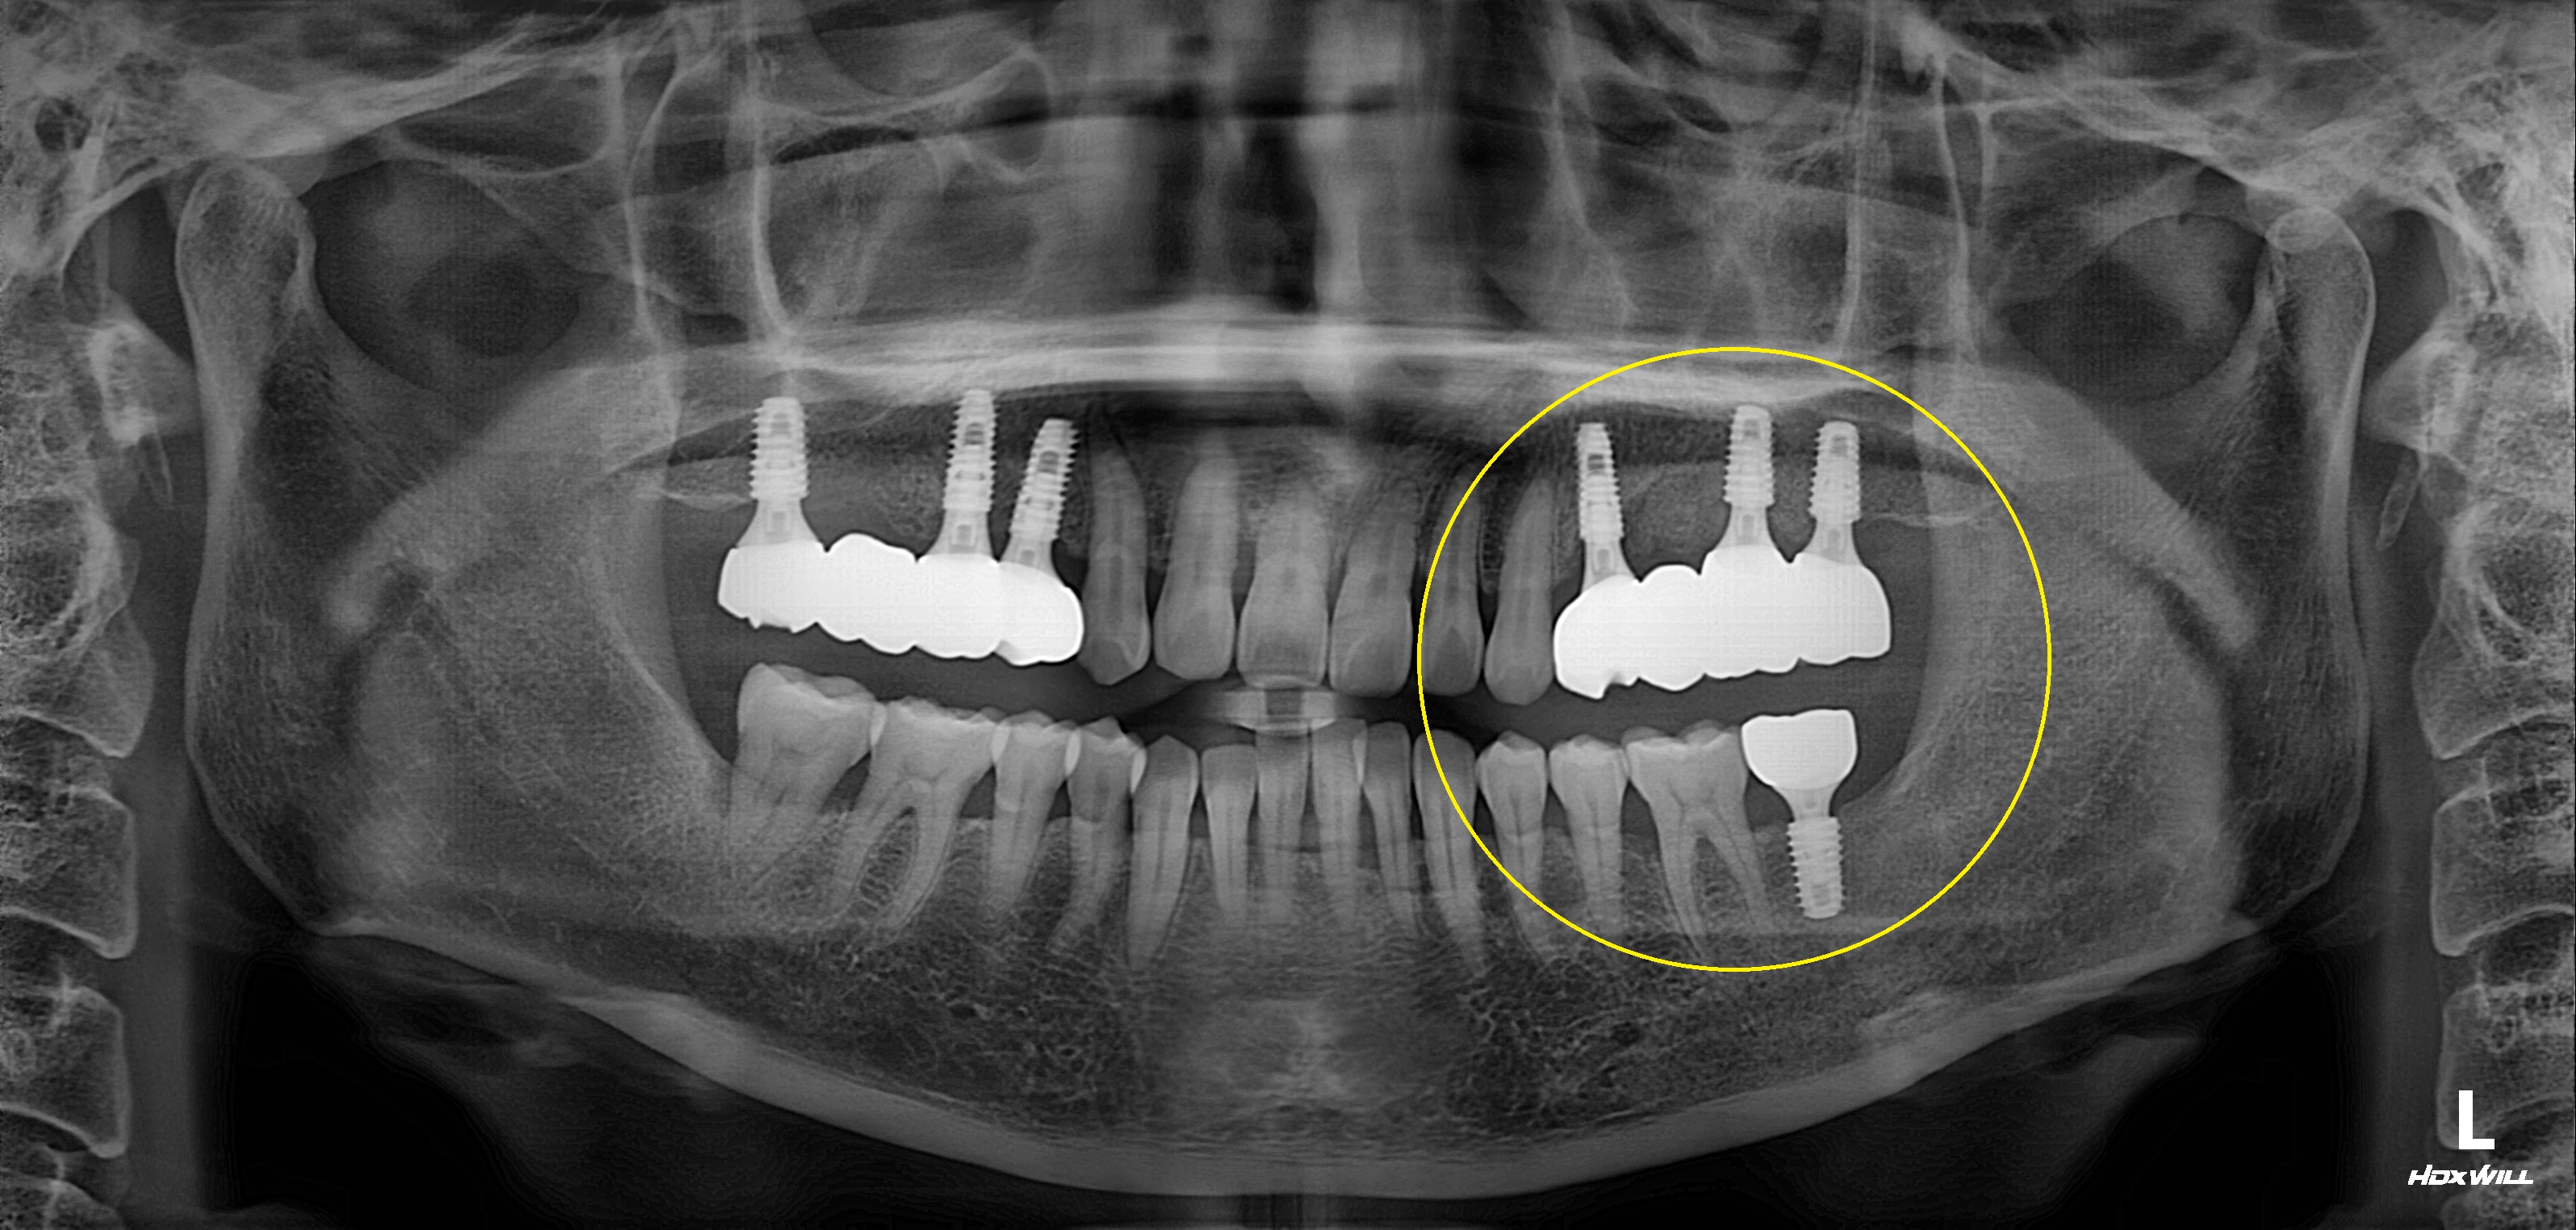

구치부 임플란트 식립사례

전후사진

수술 전

수술 후